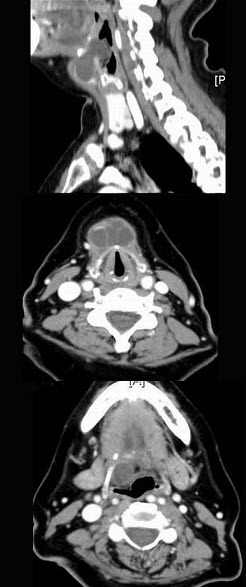

- 单项选择题女,57岁,颈部不适,CT如图所示,应诊断为()。

- C